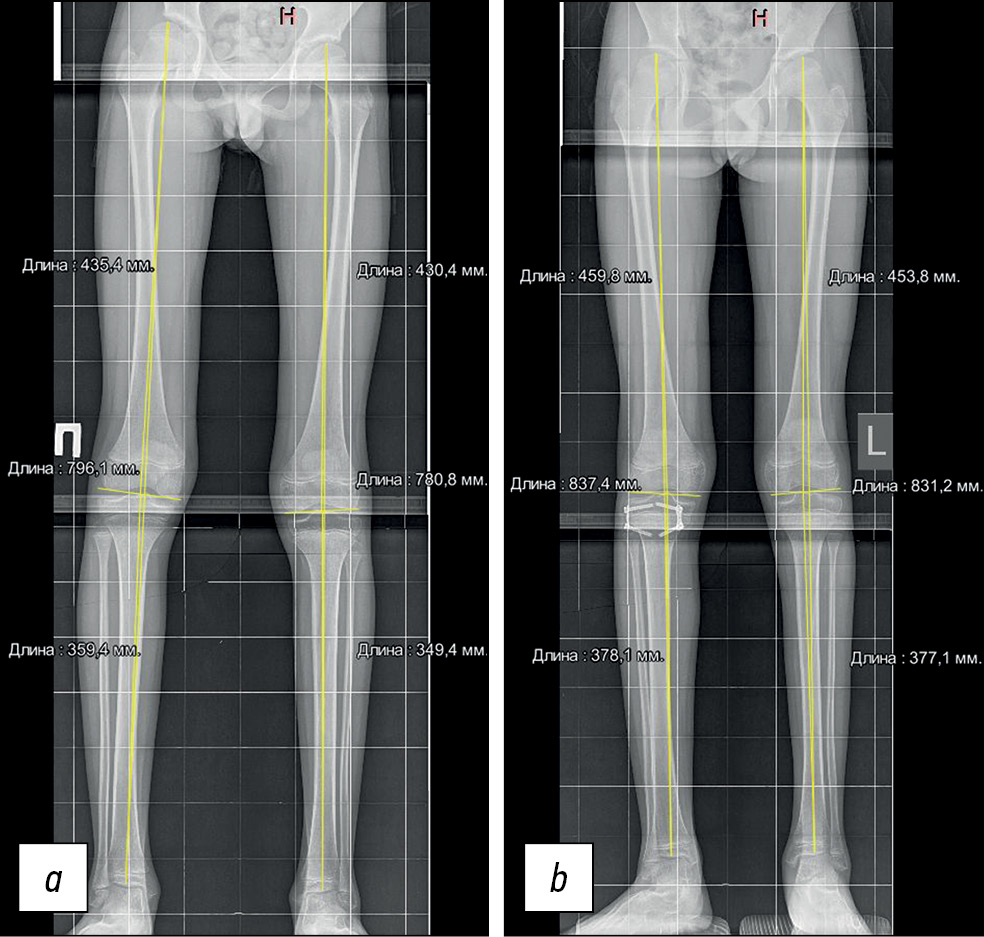

Пациент, 11 лет и 8 месяцев, с диагнозом «ДЦП, левосторонний гемипарез» поступил в Национальный медицинский исследовательский центр травматологии и ортопедии с жалобами на укорочение левой нижней конечности, хромоту и ограничение движений в левом коленном и голеностопном суставах. На обзорной телерентгенограмме нижних конечностей стоя в прямой проекции было установлено анатомическое укорочение левой нижней конечности на 15 мм (бедро — 5 мм, голень — 10 мм) (рис. 4a). За одну операционную сессию было проведено вмешательство на обеих нижних конечностях. Справа выполнен временный экстрафизарный эпифизиодез проксимального отдела правой большеберцовой кости 8-образными пластинами. Слева — тенотомия полусухожильной мышцы, апоневротомия полумембранозной, икроножных мышц по Strayer, укорочение сухожилия задней большеберцовой мышцы за счёт её дублирования. Гипсовая иммобилизация левой нижней конечности составила 4 недели. Пациенту проводились контрольные измерения на телерентгенограмме нижних конечностей в сроки 6 и 10 месяцев после операции. На 10-й месяц установлена одинаковая длина конечностей, (рис. 4b), металлоконструкции с проксимального отдела правой большеберцовой кости были удалены.

Рис. 4. Телерентгенограмма стоя в прямой проекции: a — до операции, b — перед удалением металлоконструкции, скорость коррекции составила 10 мес.